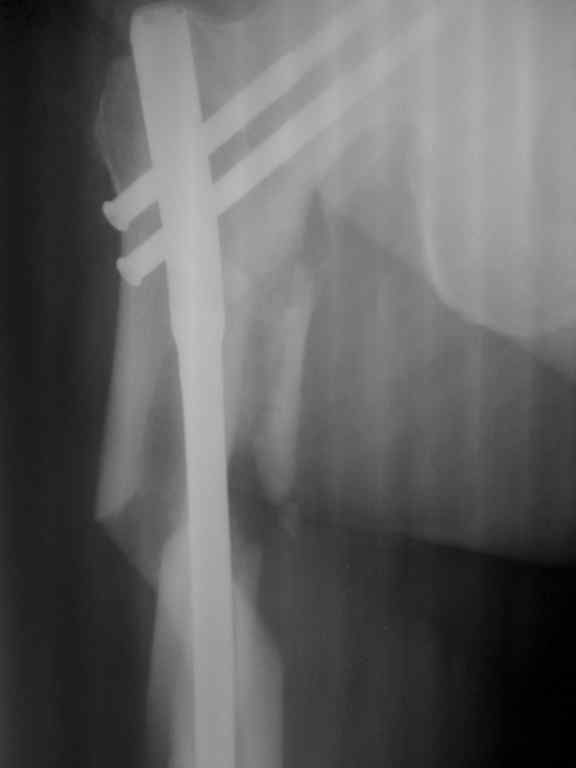

Что то по представленным рентгенограммам не пойму, что же произошло. Ножка вне диафиза, но как она вышла из канала? Даже странно.

такое впечатление, что штифт сломался на 2-ом проксимальном винте и таким образом послужил распоркой между проксимальным и дистальным отломками (линия перелома была косая, насколько я понимаю)

Сломался гвоздик, видимо, по нескольким причинам - оставался небольшой варус, тонкий гвоздь, несвоевременная динамизация (про последние - предположение).

Р-гр после операции

|